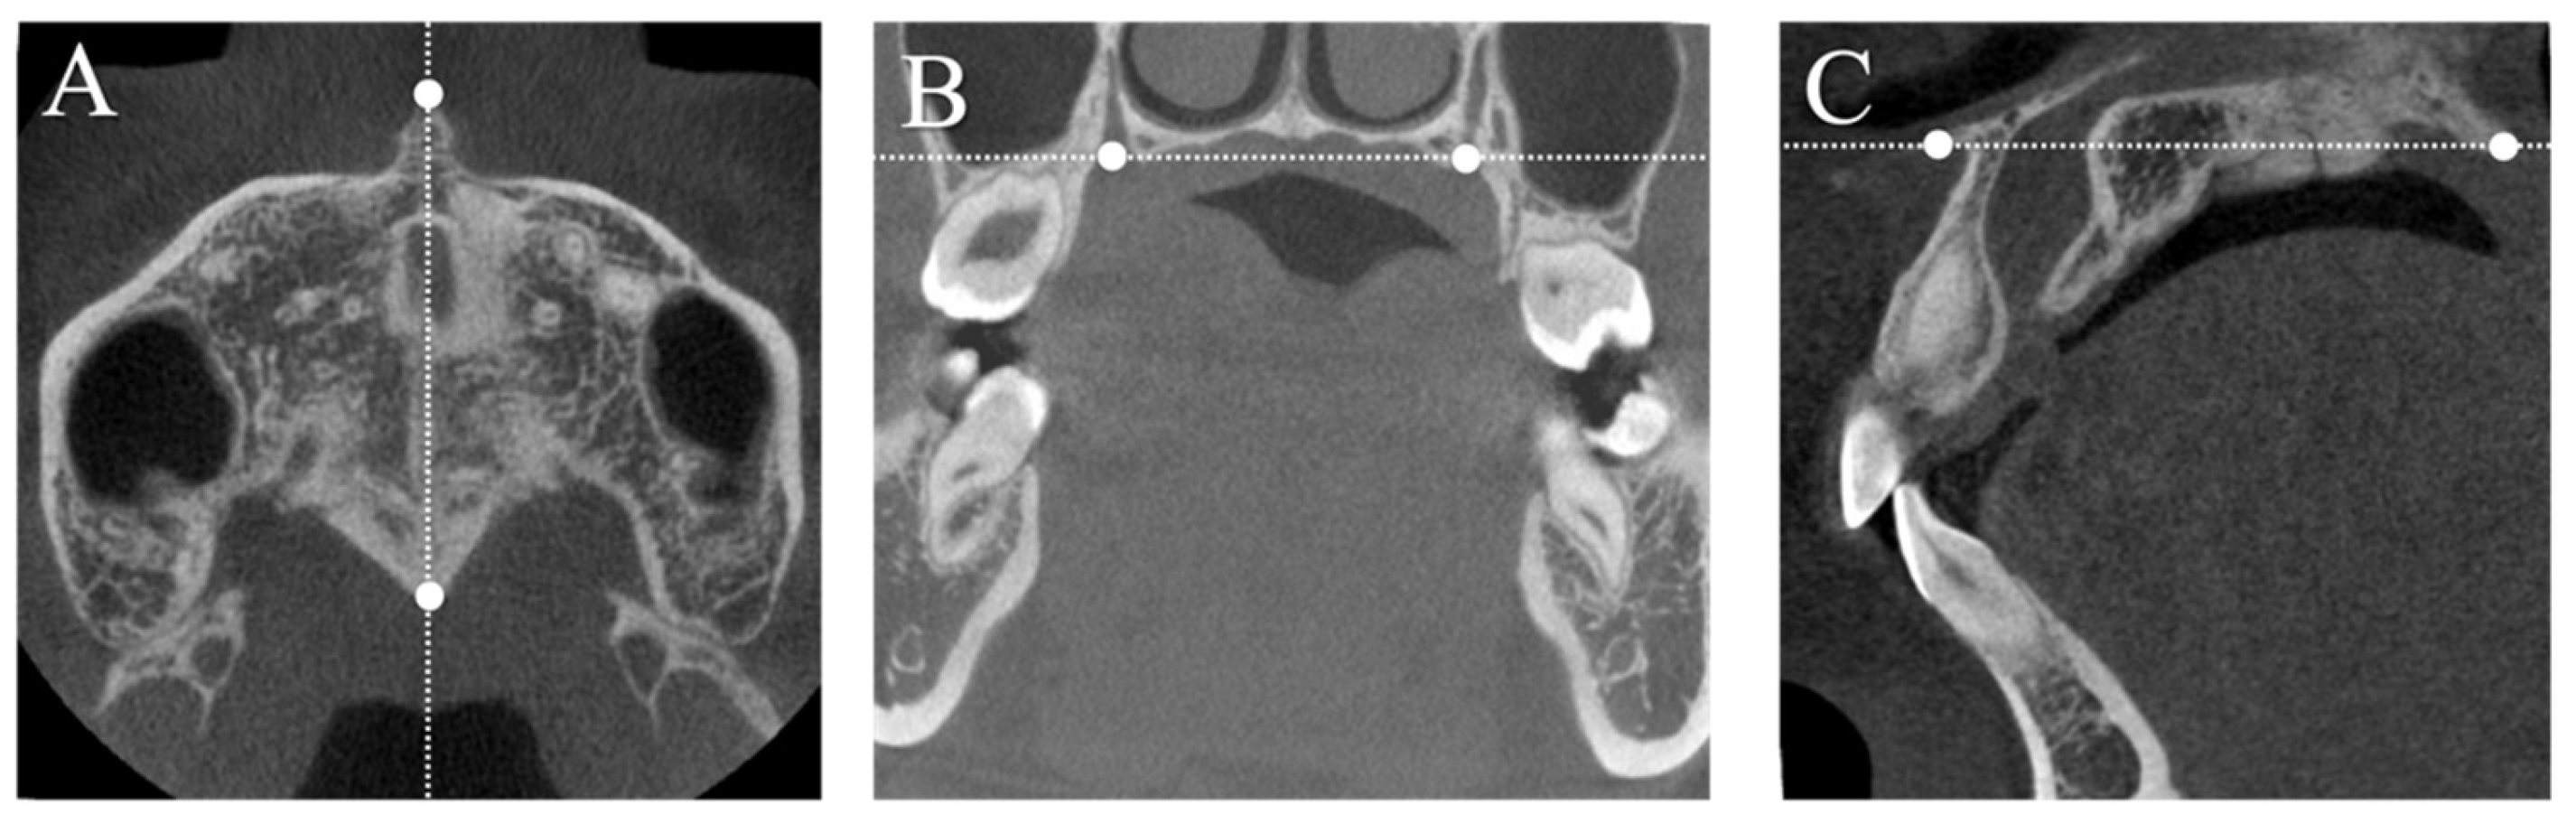

2.2. Measurements